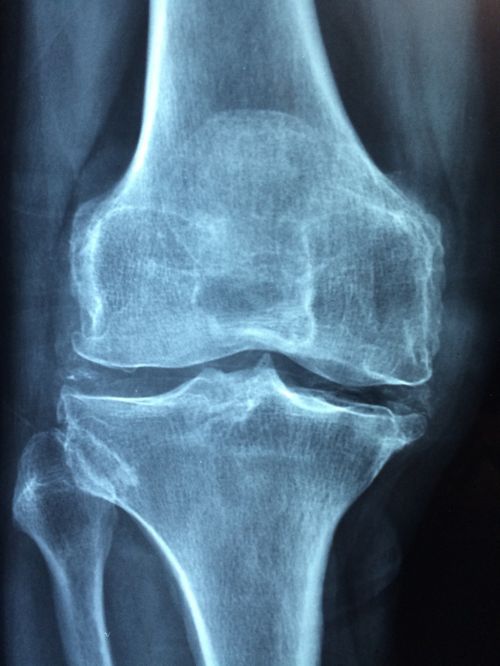

Диагностика остеоартрита

Врач спросит пациента о симптомах и проведет физическое обследование.